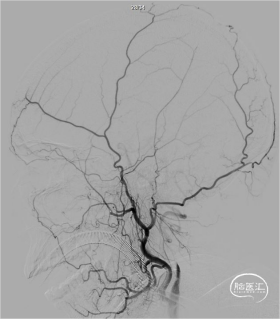

DSA示右侧颈内动脉闭塞。

静待约5min后,采用SWIM技术取栓,一次再通,造影示三级血流。

术后右侧颈内动脉造影可见血流通畅,右侧大脑中动脉显影良好。麻醉苏醒,左侧肢体肌力3级。